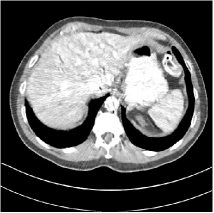

Refer to caption

Fig. 4: FBP images of test examples.